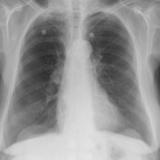

Bronch Cyst 1

arrow